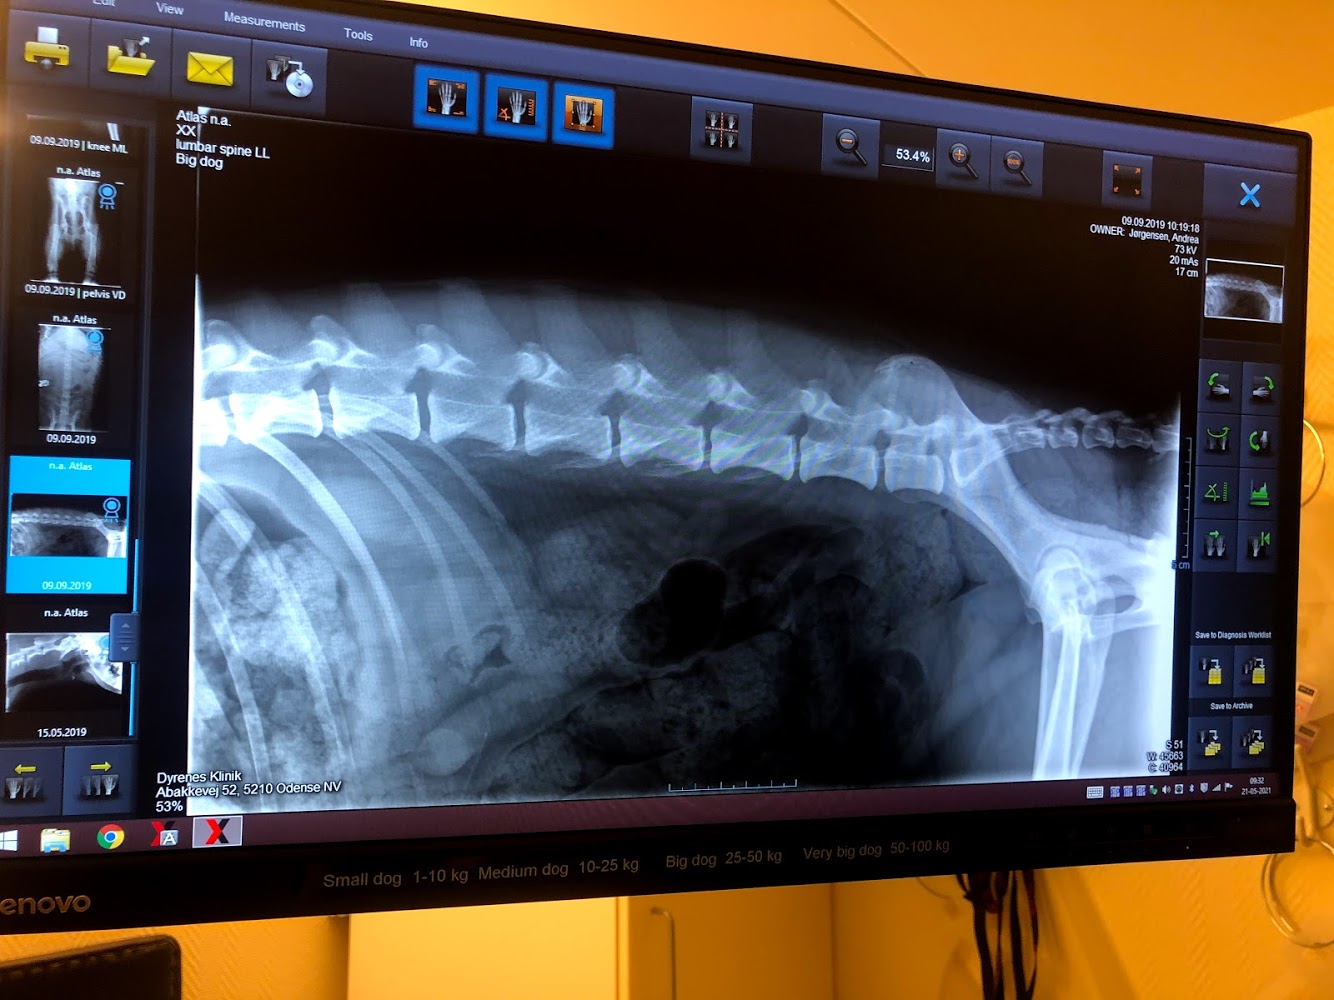

Vi kan ikke se alt under overfalden. For at kunne stille en sikker diagnose, er det somme tider nødvendigt for os at få røntgenfotos.

Vi råder over et moderne digitalt røntgenanlæg, som hjælper os til at tage de bedst muligt røntgenbilleder, og giver os mulighed for at have svar relativt hurtigt.

Vi bruger som sagt røntgen til at stille diagnoser, ved f.eks. halthed, indtag af fremmedlegemer, smerter i bevægeapparatet m.m. Derfor kræver en røntgenfotografering også ofte at dyret får en beroligende sprøjte inden. Så vi mindsker ubehag for dem, men samtidig kan tage præcis billeder.

Vi er godkendt af Dansk Kennelklub til at tage røntgenfotos til bedømmelse for HD,AD og OCD.